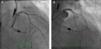

Following local anesthesia, a 6-Fr sheath was inserted into the right femoral artery. After performing a contrast study of the aorta and both iliac arteries, the patient was considered a candidate for using the assist device. A 14-Fr sheath was then placed in the left femoral artery. After administration of 5000 units of unfractionated heparin (UFH), an angiographic pigtail diagnostic catheter (Cardinal Health) was used to deliver a specific 0.14-inch guidewire to the LV. The diagnostic catheter was then removed, and the Impella CP® pump was advanced over the wire across the aortic valve under angiographic guidance (Figure 1A). The pump was started, with a maximum of 3.5 l per minute of circulatory support necessary to maintain the patient hemodynamically stable during the procedure.

Case 1. (A) The right anterior oblique caudal view reveals the saphenous vein graft (SVG) to the first obtuse marginal before intervention and the Impella CP® device. (B) Distal embolic protection device, Emboshield NAV (Abbott Vascular), deployed in the distal portion of the SVG. (C) The right anterior oblique caudal view shows the final angiographic result.

The SVG to the OM1 was intubated with a 6-Fr Amplatz Left 1 catheter (Cardinal Health). A distal embolic protection device, the 6-Fr Emboshield NAV (Abbott Vascular), was gently passed into the SVG across the target lesion and was deployed at the distal portion of the graft (Figure 1B). After pre-dilation of the target lesion with a 3.5×20-mm TREK balloon (Abbott Vascular), a 4.0×28-mm Xience stent was successfully deployed in the SVG. Next, the stent was post-dilated with a 4.5×15-mm Quantum™ Maverick™ balloon (Boston Scientific) at 18 atm. The Emboshield NAV basket was then carefully withdrawn. Aspiration was performed to clear the guide catheter of any debris and thrombi and ensure that none of the contents of the basket remained in the guiding catheter (Figure 1C).